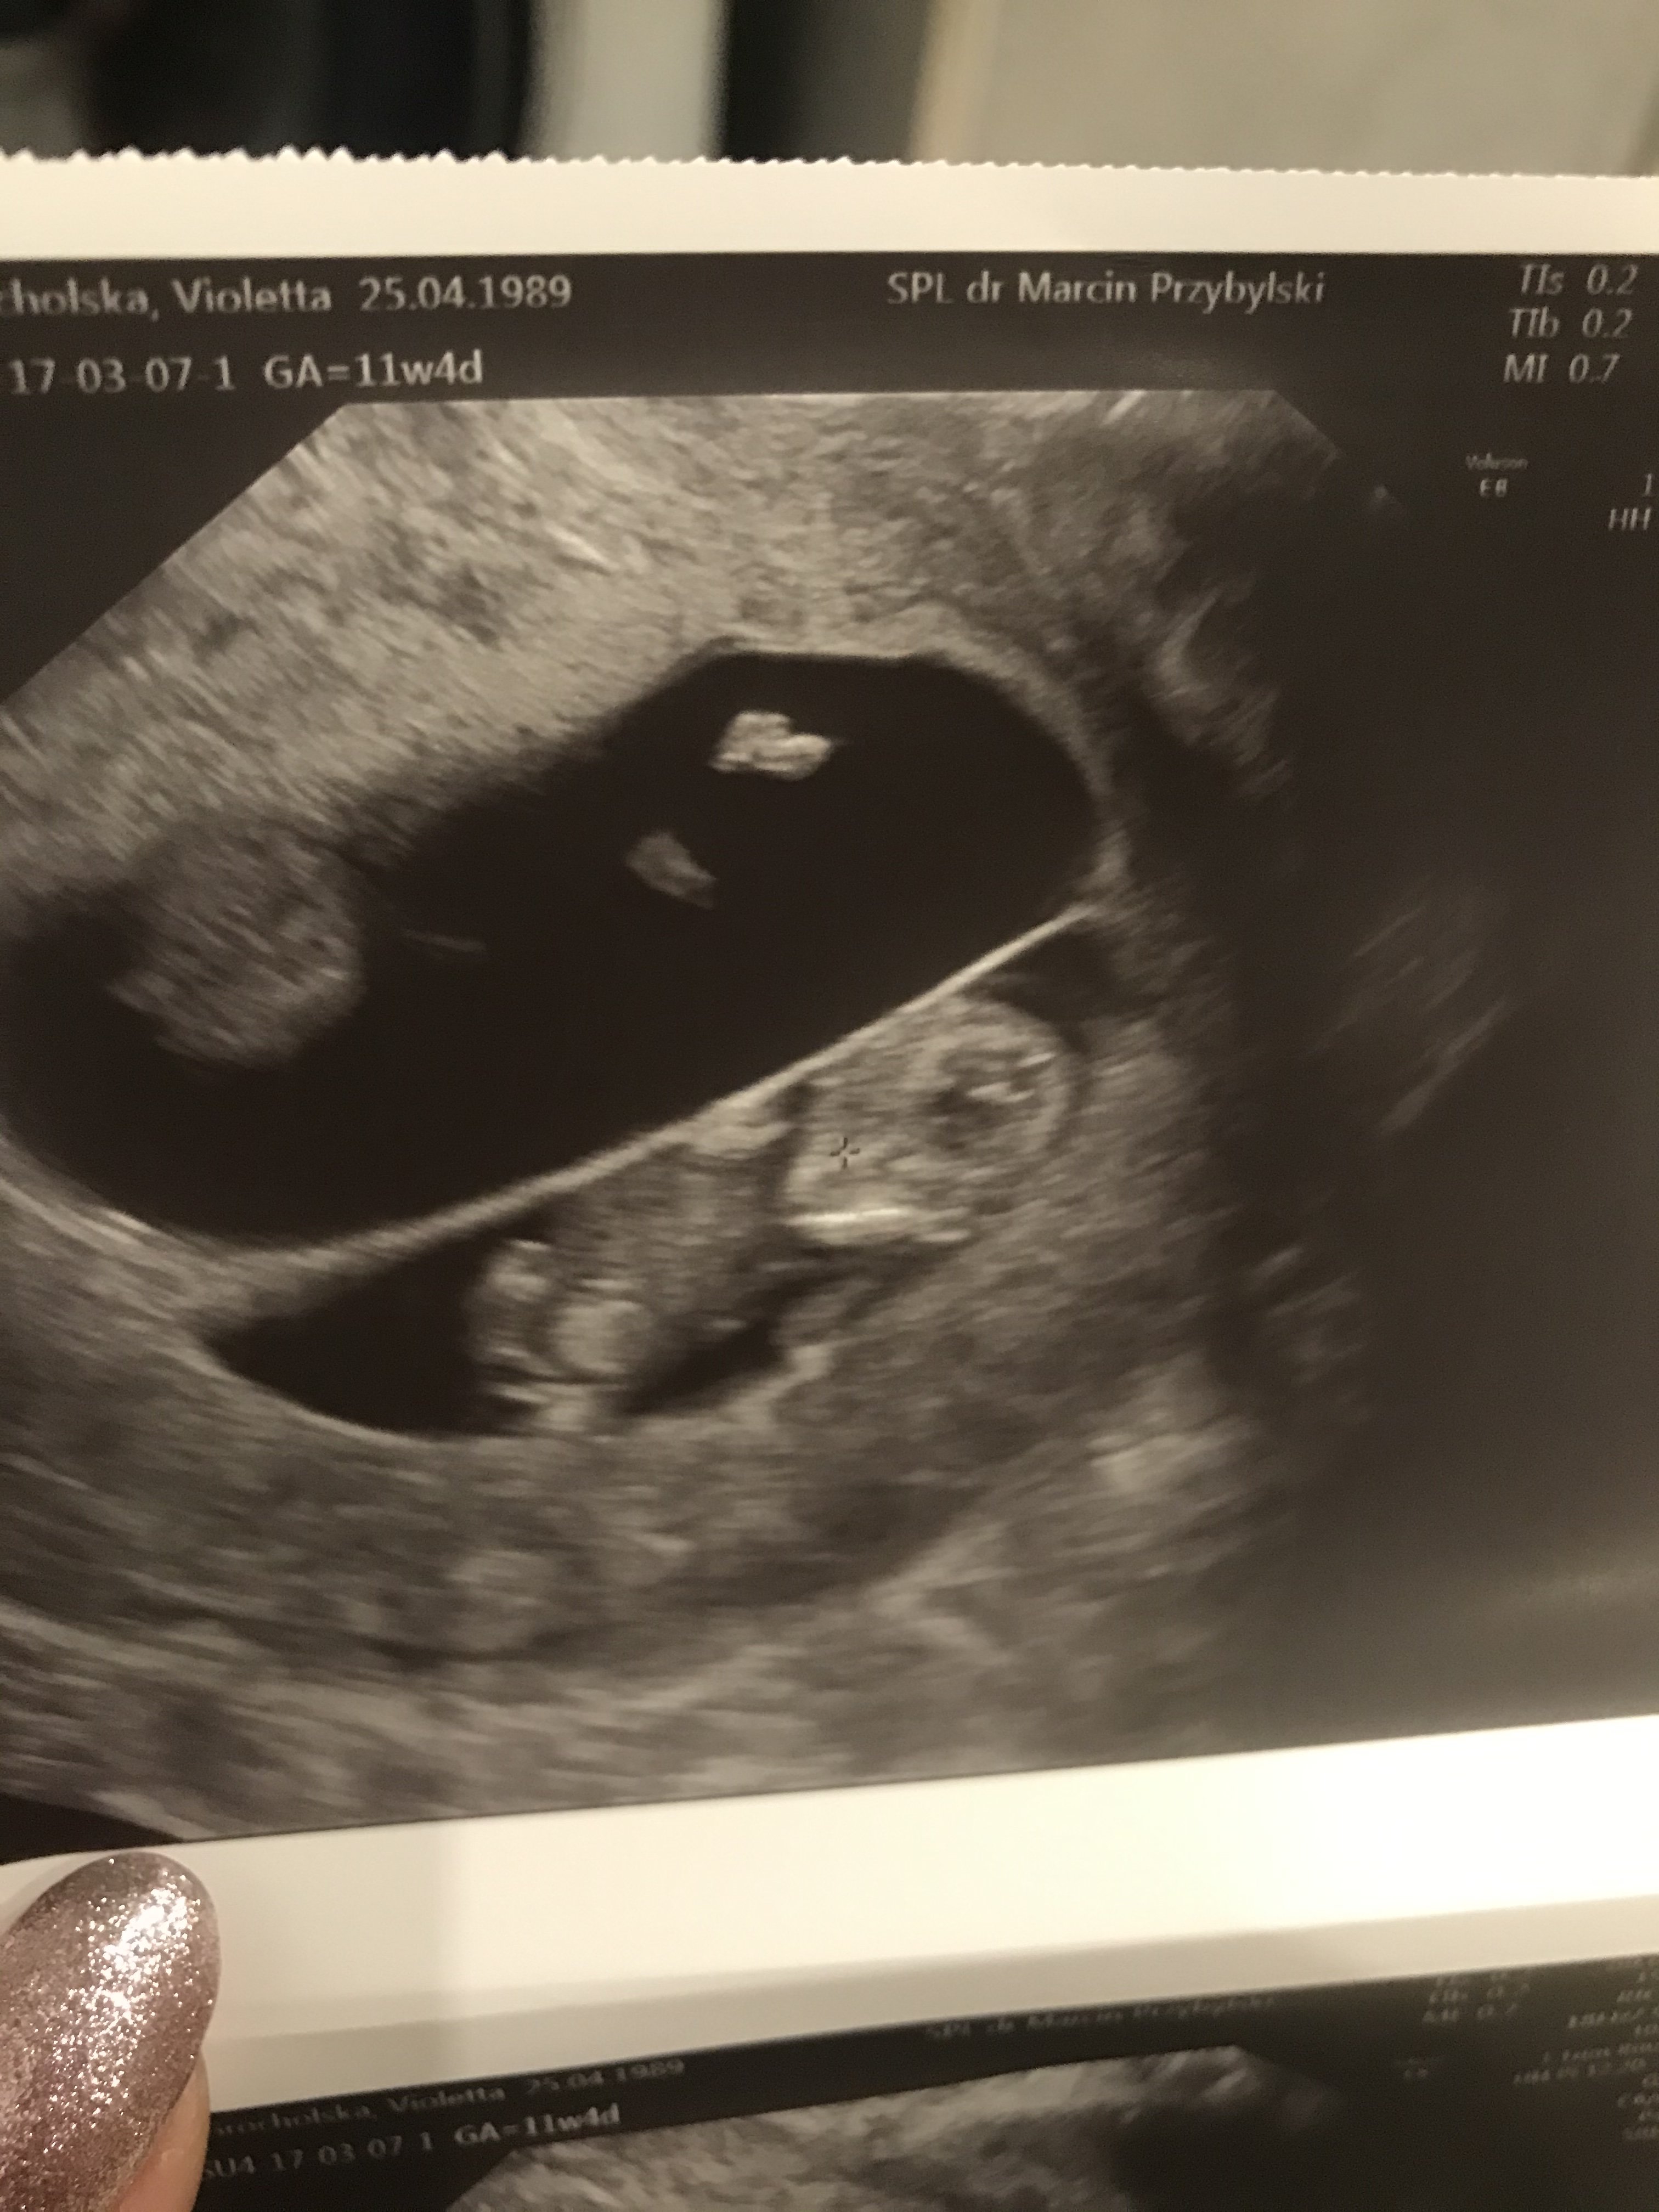

Już po wizycie. Dziś bez zdjęcia(chociaż na ekranie podziwialiśmy. Mąż nawet nóżki widział

). Kijanka mierzy niemal 3 cm (wg Męża 2,7, wg mnie 2,9). Przełom 10 i 11 tygodnia. Od razu kazali mi siusiać do kubeczka i krwi utoczyli. W sumie nie wiem na co, ale na wszystko podobno.

Słodka byłam, jestem i będę, więc staram się cukier ograniczać jak najbardziej (tym bardziej, że najpewniej wkrótce odstawię metforminę). Następna wizyta za 4 tygodnie. Eh...